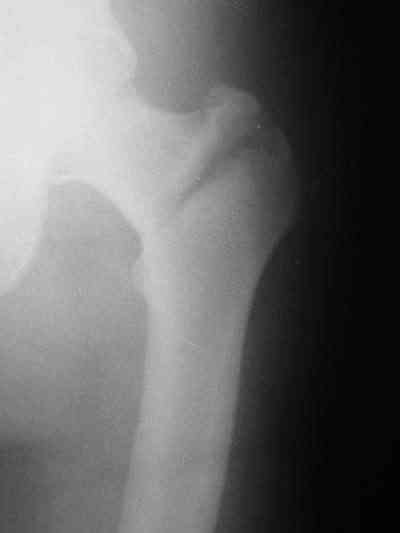

Около 10 дней назад выполнил остеосинтез бедренной кости LC-DCP и DHS по поводу фрагментарного оскольчатого перелома в средней трети и чрезвертельного перелома.

Снимки в приложении.

В приложении и имеющийся в наличии брейс. Приношу извинения за низкое качество снимков.

Качество снимков приемлемое. С нагрузкой категорически не надо спешить - только при уверенных рентгенологических признаках сращения на обоих уровнях в данном случае. Т.е. не только на диафизе, но и в вертельной области. При безупречном синтезе DHS ранняя нагрузка в этой зоне была бы безопасна, все определялось бы сращением диафиза. А поскольку винт в DHS сделали ну о-очень короткий, то ойкнуть не успеете, как

проксимальный отдел бедра в варус кувыркнется.

Уважаемый Никита, очень меня расстроило не качество снимков, а сам остеосинтез. Вертельный перелом, пожалуй, еще срастется. А диафиз может преподнести ожидаемое, предуготованное осложнение: несращение и перелом импланта, даже если это суперфмрменная пластина.:(